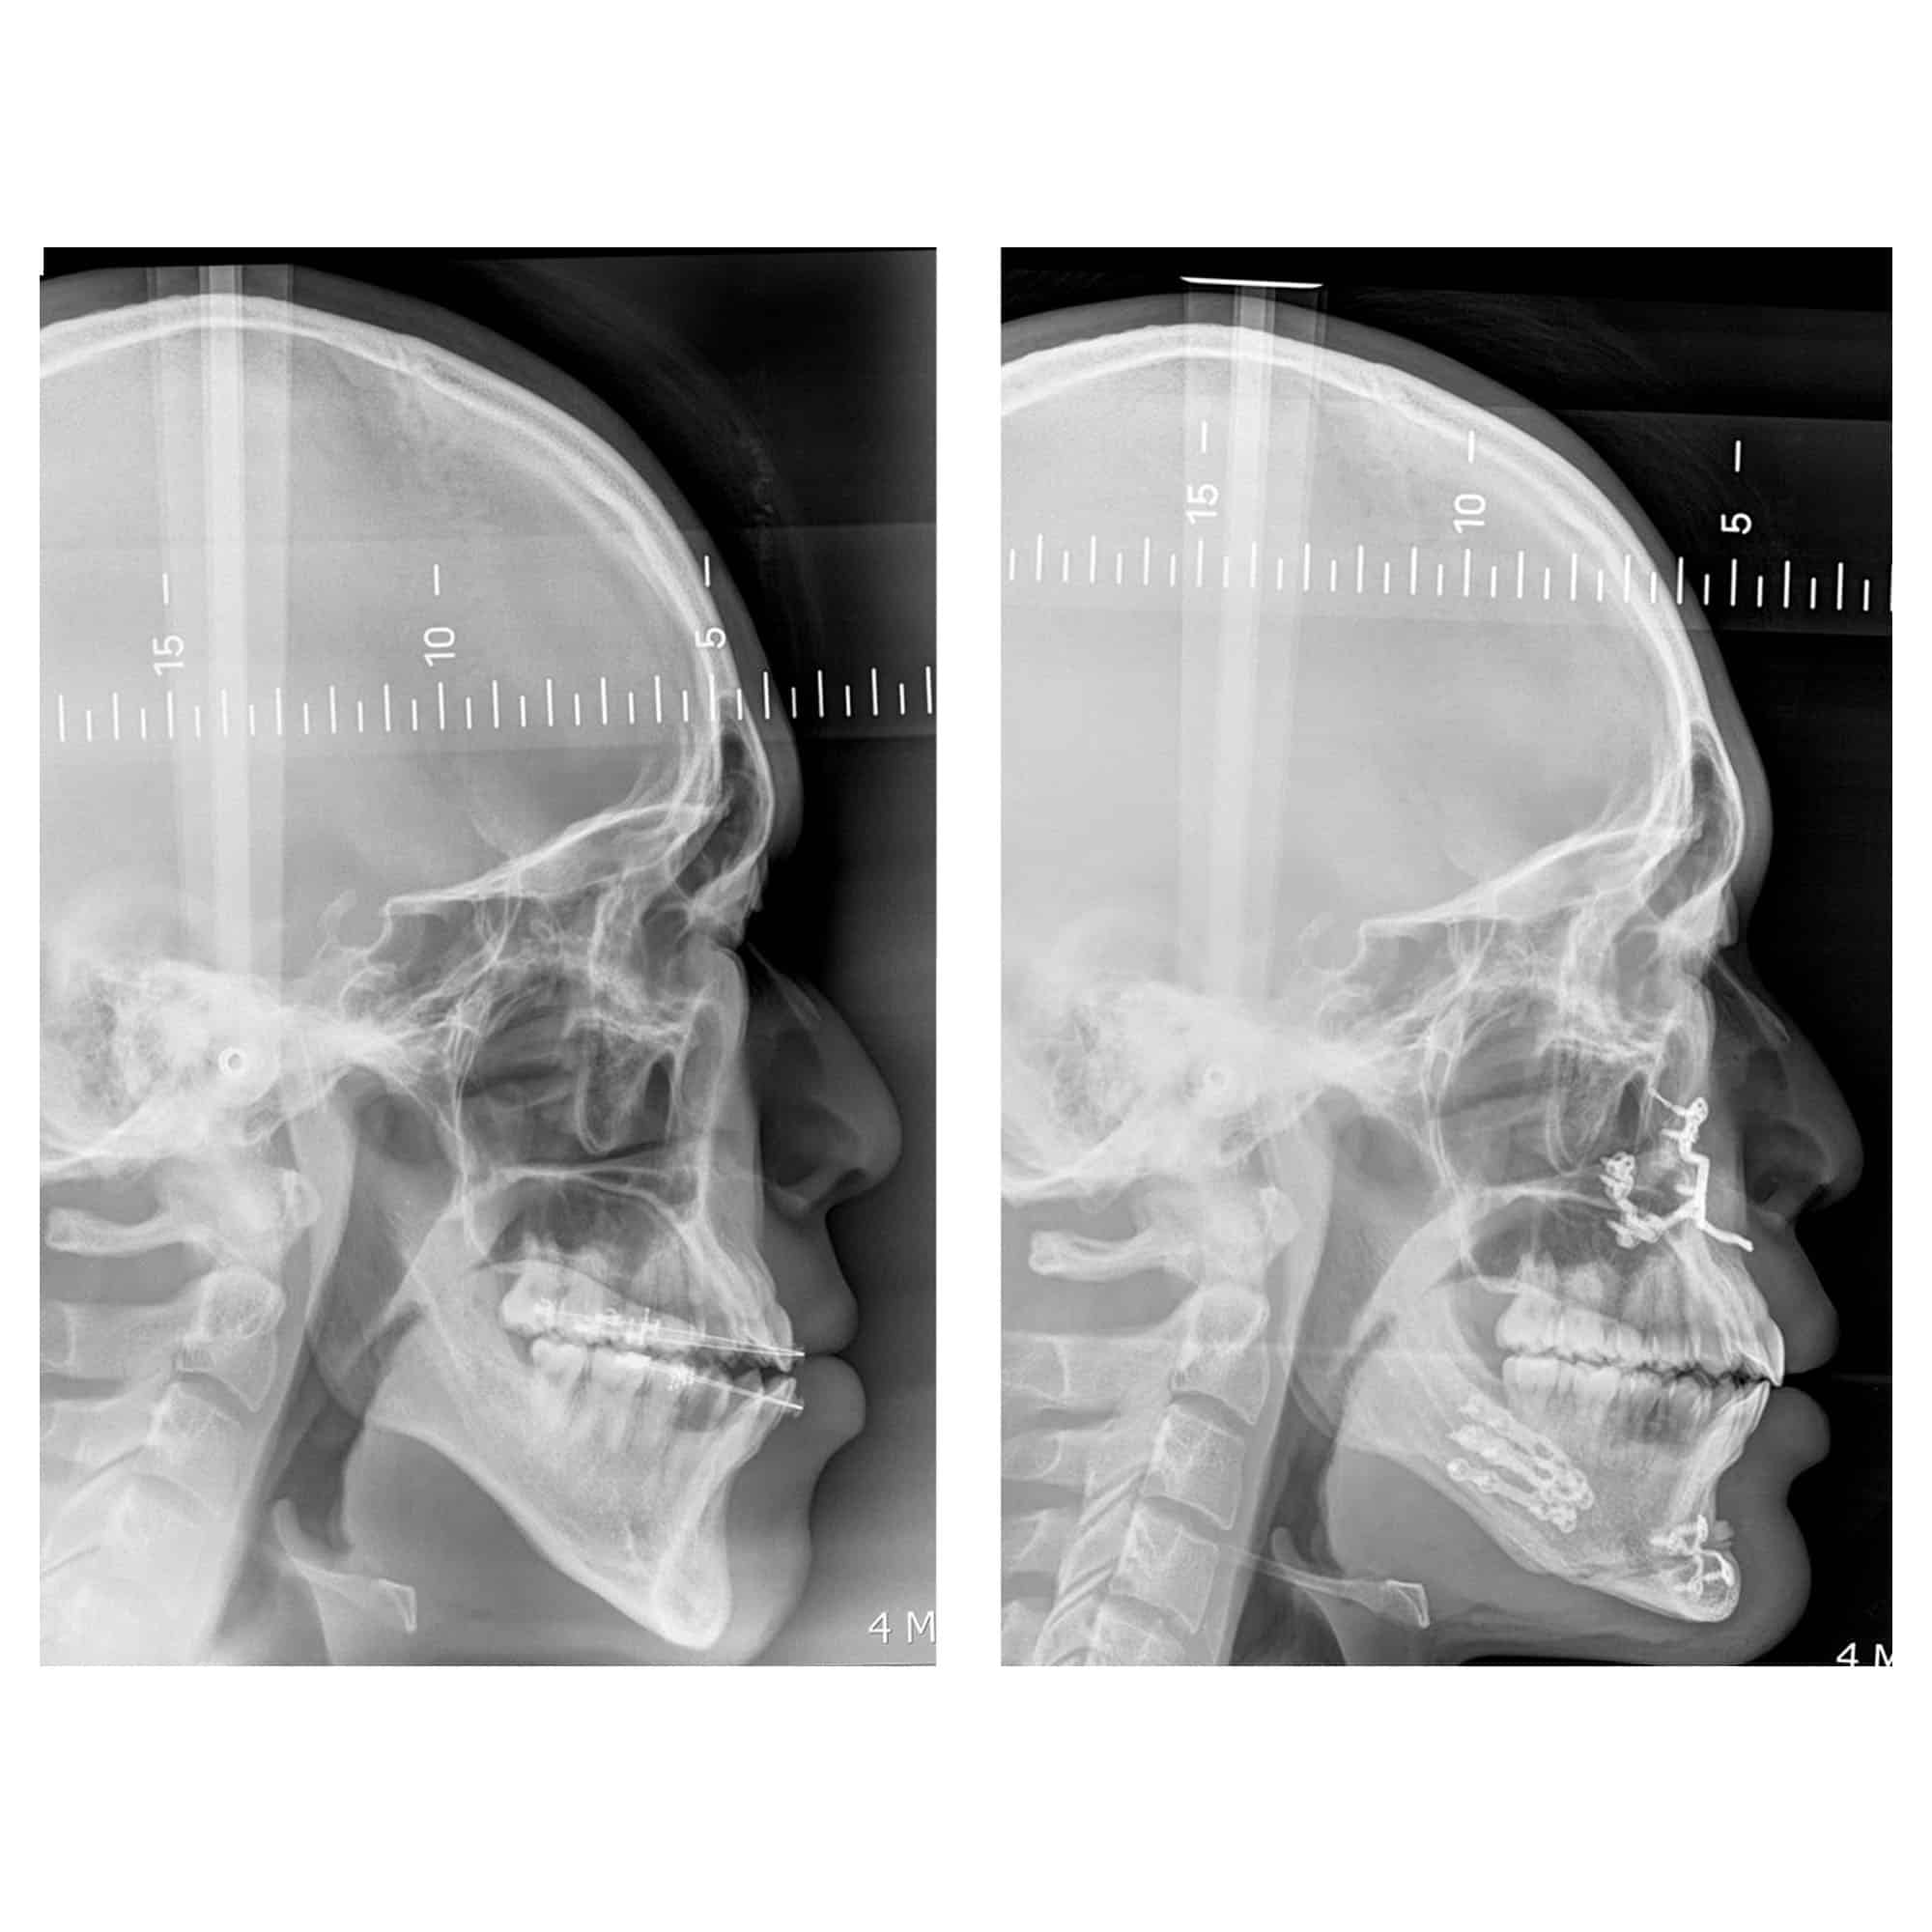

Génioplastie Paris : un exemple de génioplastie chez une patiente en traitement d’orthodontie

Voici le cas d’une patiente en Classe I squelettique mais en Classe III dentaire, du fait de la vestibulo-version des incisives mandibulaires (incisives rentrées vers l’intérieur) avec excès vertical antérieur. Cette patiente a été traitée par une rotation anti-horaire de la mandibule et une génioplastie, qui ont permis de corriger l’aspect inesthétique de départ. L’impact est aussi bien esthétique que fonctionnel, avec une amélioration de la qualité du sommeil.

Remarque sur le diagnostic et le plan de traitement : il ne fallait pas avancer le maxillaire (le haut) en raison des retentissements esthétiques néfastes potentiels mais bien faire un geste sur la mandibule (le bas). Dans tous les cas, mais encore plus ici, l’expérience du chirurgien orthognatique est cruciale afin de bien déterminer le plan de traitement adapté.

Remarque sur le traitement orthodontique associé : une fois l’intervention chirurgicale terminée, l’orthodontiste a repris son traitement et “égressé” les dents mandibulaires (du bas) pour fermer la béance postérieure générée par le mouvement chirurgical.